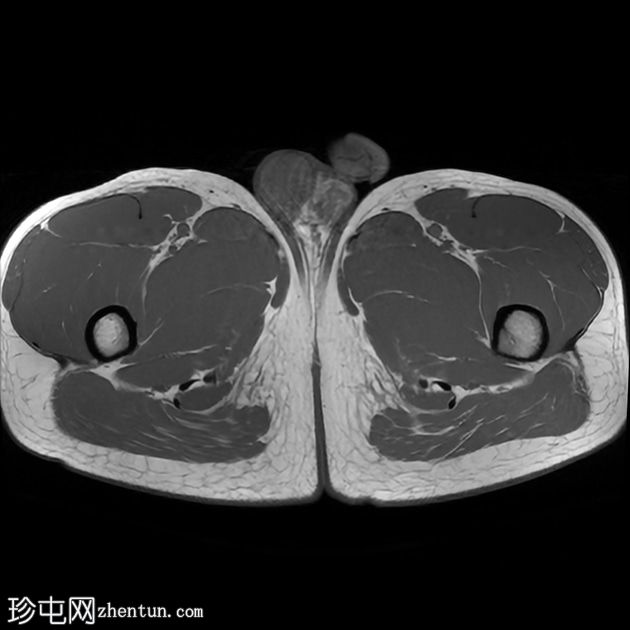

轴位

T2加权像

前列腺大小为32.8 x 41.5 x 34.7 mm(前后径 x 宽度 x 头尾径),体积为25.88 ml,属于正常范围。前列腺中央可见一逗号状囊性占位性病变,大小为17.3 x 12.1 x 9.3 mm(头尾径 x 前后径 x 宽度)。可见囊肿与前列腺尿道相通。囊内未见可疑内容物——具体而言,未见囊内出血或碎屑——弥散加权成像结果为阴性,提示无囊内感染。

本例为一例发生于青年人的单纯性逗号状中央型前列腺内囊肿。

根据囊肿位于前列腺中央或中线(精阜水平)、患者年龄(二十岁左右)以及无前列腺外延伸和明显的尿道交通,前列腺囊肿是首选诊断。苗勒氏管囊肿通常难以排除。患者的年龄、无前列腺外延伸以及疑似尿道交通使该诊断的可能性降低。